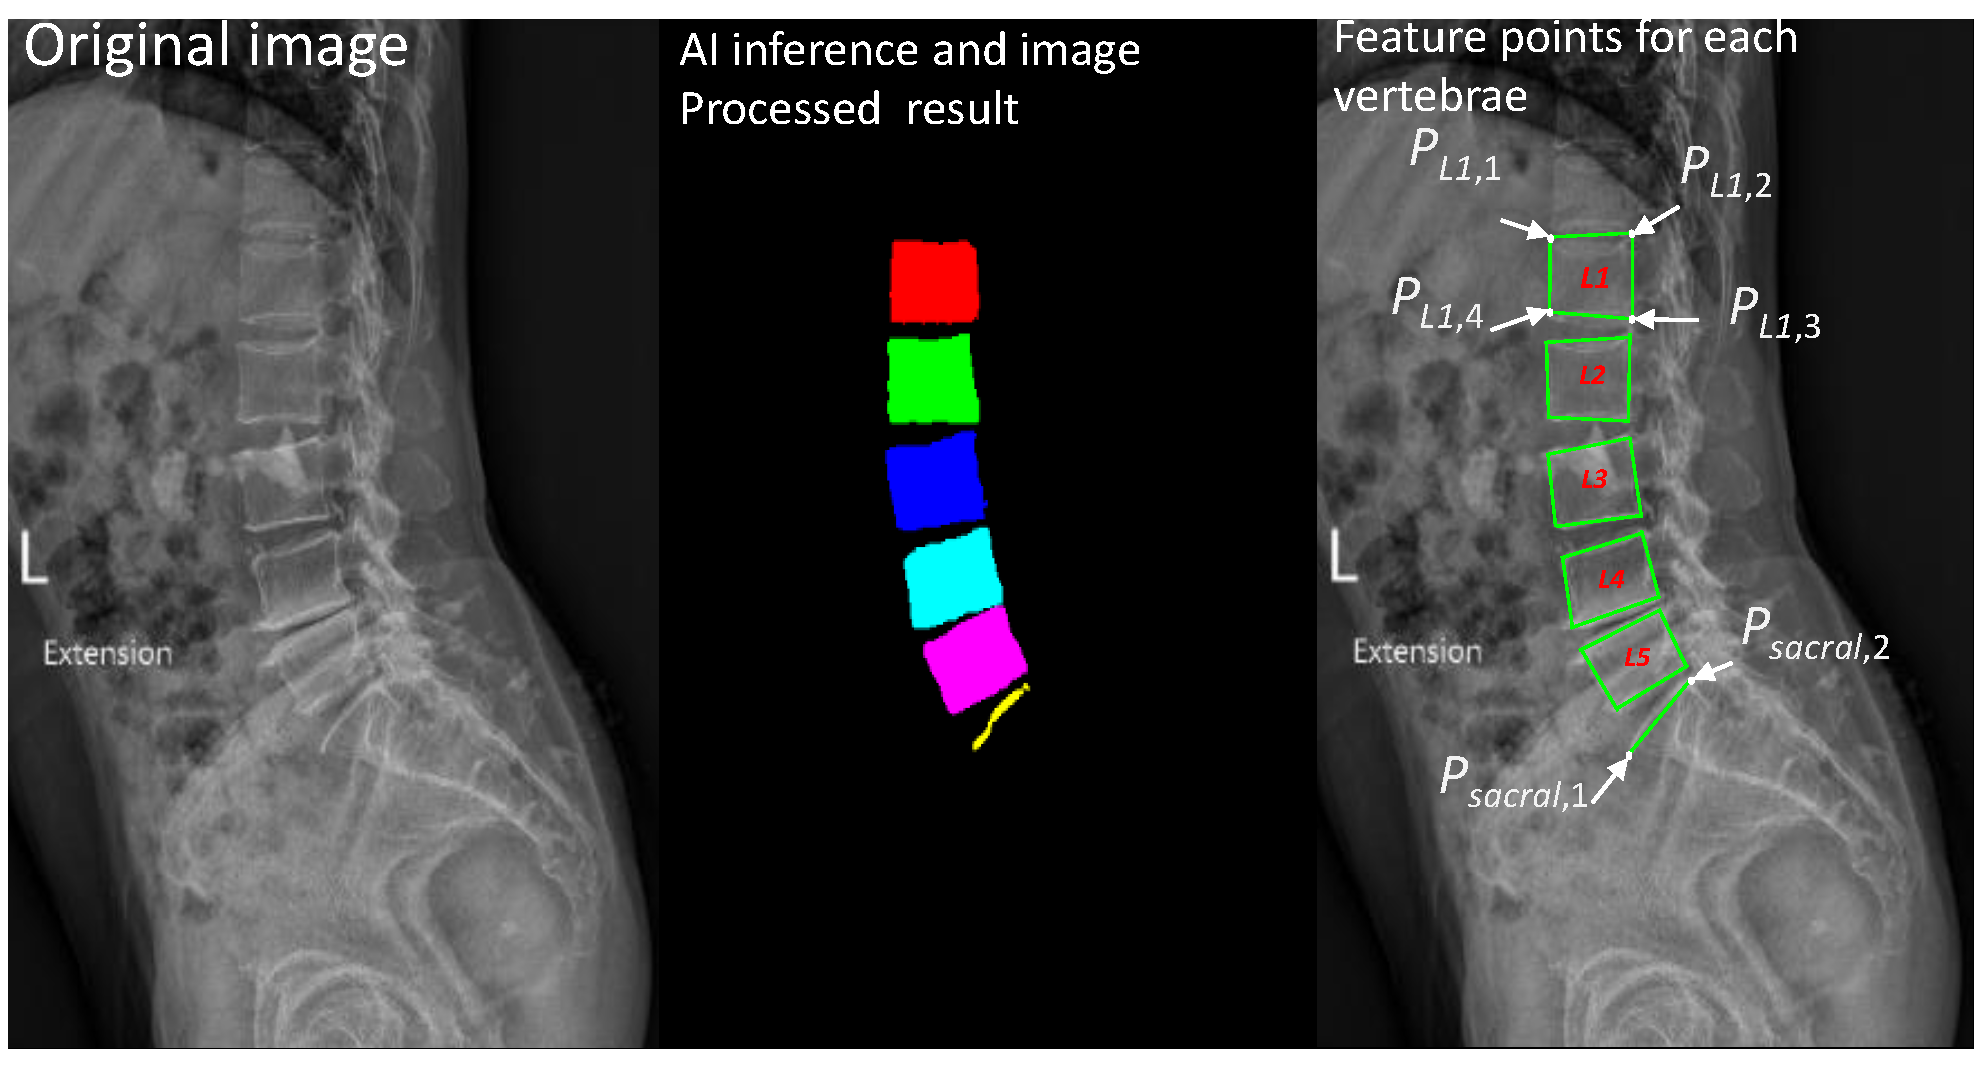

There are five lumbar vertebrae in total. The quadrilateral of each vertebra has four extreme points, where . The upper-left, upper-right, lower-right, and lower-left points of a lumbar vertebra are , , , , respectively. The sequence of the four points of each vertebra runs counterclockwise from the upper-left point. In addition, the top plate of the sacrum is represented by two points, namely the left and right points, as illustrated in Figure 4.

Figure 4.

Original image (left), processed image (middle) with different colors to distinguish vertebrae from to , and calculated feature points of each vertebra and sacrum (right).

After these feature points are detected, a P-grade for the difference between the left and right vertebral segments is calculated, with a value >20% indicating abnormality. The process of determining abnormality from one X-ray image is illustrated in Figure 5.